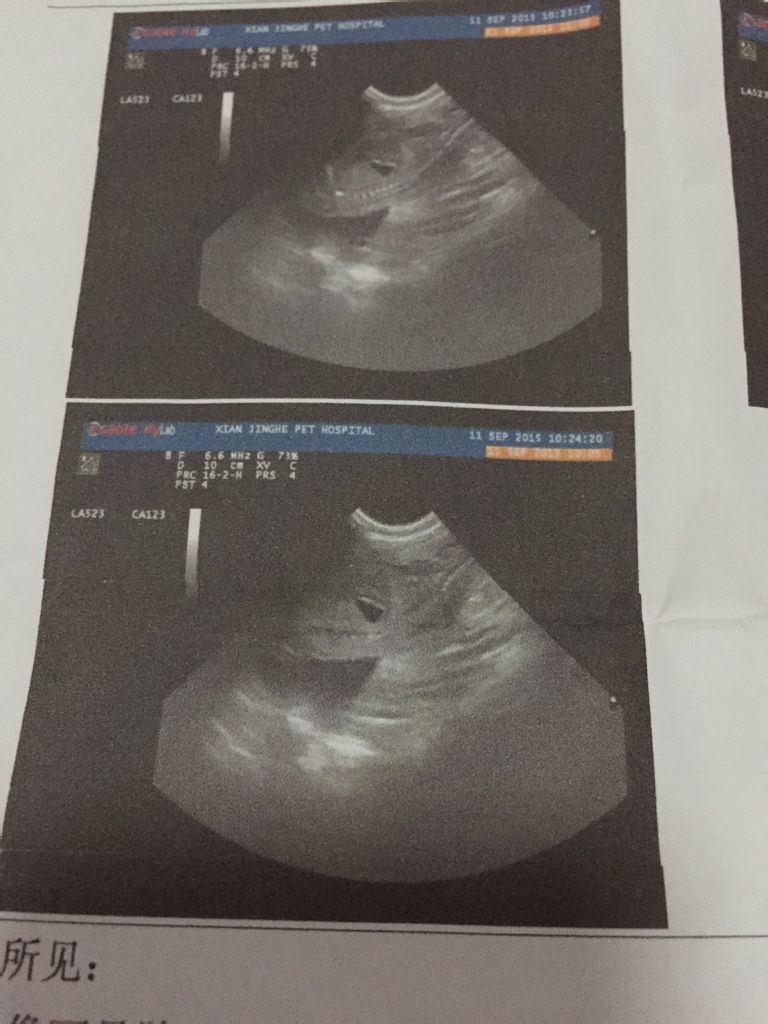

一个月前捡的流浪狗原来是怀孕了 我也不知道它怀了多久 做了b超 看起来狗狗挺大的 不知道什么时候生

一个月前捡的流浪狗原来是怀孕了 我也不知道它怀了多久 做了b超 看起来狗狗挺大的 不知道什么时候生啊 狗狗什么情况下是快生了  还有 我没有接生过 到时候改怎么办 求帮助